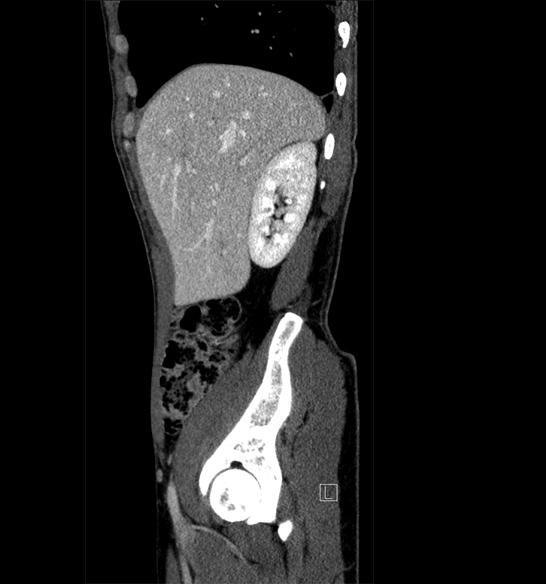

Body

Covers abdominal CT anatomy.